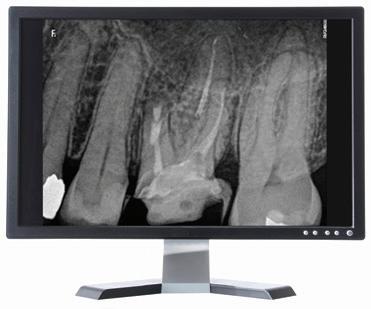

Ny, trådløs endomotor gir maksimal valgfrihet!

Nye Sendoline Endo Motor kan brukes med både roterende og resiprokerende filsystemer!

Stor valgfrihet! Bruk den bare som endomotor, som endomotor med apekslokator eller bare som lokator.

Vinkelstykket har slank, smal hals og et lite hode som kan roteres 360°. Dette gir deg enda bedre og enklere tilgjengelighet i munnen, med optimal sikt.

Rotary S5 System

Reciprocating S1 System

16.990,-